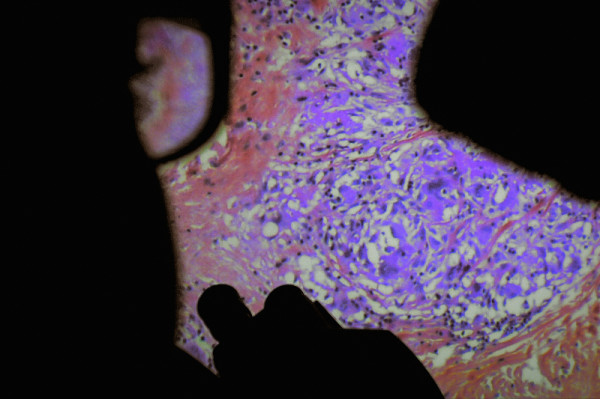

Tras un comienzo desconcertante, de lo que parece ser una ronda del equipo de seguridad por los sótanos de un hospital, asistimos a una conversación de UCI entre unas enfermeras de guardia, en donde comentan su situación laboral, la falta de personal etcétera y el estado de algunos pacientes. Y seguidamente la cámara muestra el interior de un cuerpo, de un cerebro en concreto, con sus membranas y conductos, mientras es sometido a una operación quirúrgica. De fondo suena el murmullo sordo de los médicos, la vida exterior. Salvo algunos planos que muestran a pacientes que se mueven por pasillos, ancianos seniles (con agotadores y larguísimos planos-secuencia), esas imágenes del interior viscoso del cuerpo humano son una muestra de lo que vamos a ver a lo largo de todo el documental: una exploración en los intestinos; una extracción de próstata; la operación en un ojo; un catéter en un pene, etc. Y entremezcladas de vez en cuando algunas conversaciones banales y rutinarias entre médicos, mientras las herramientas horadan el interior de los pacientes. No son imágenes agradables las que se ven en pantalla, pero especialmente parecen poco aptas para aprensivos las de la cesárea en vivo, las que muestran una mama con cáncer que ha sido cercenada para ser analizada en el laboratorio o las de la operación de columna vertebral.